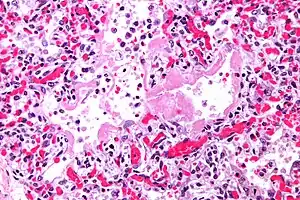

| Micrograph showing hyaline membranes, the key histologic feature of diffuse alveolar damage. H&E stain. | |

- The edema contributes to the deposition of a hyaline membrane (composed of dead cells, surfactant, and proteins) along the alveolar walls. Hyaline membranes are characteristic of DAD.

In order to make a diagnosis of DAD a biopsy of the lung must be obtained, processed, and examined microscopically. As described above, the hallmark of diagnosing DAD is the presence of hyaline membranes.[1] Most frequently DAD is associated with ARDS, but since there are clinical criteria (see Berlin criteria above) upon which we can diagnose ARDS, it is often unnecessary in all cases to obtain invasive biopsies of the lung. Additionally, there are limitations of the biopsy test since it is possible to sample a potentially normal area of lung even though there is DAD in the rest of the lung, resulting in a false negative.[1]